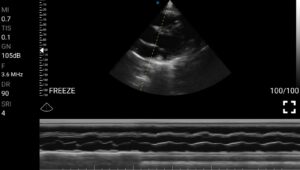

Παραδείγματα

Ολες οι παραπάνω απεικονιστικές εξετάσεις έχουν ληφθεί από φορητή συσκευή όπως: Apple Iphone, Tablet, Samsung Mobile Phones και διάφορες άλλες φορητές συσκευές.

Παραδείγματα Video